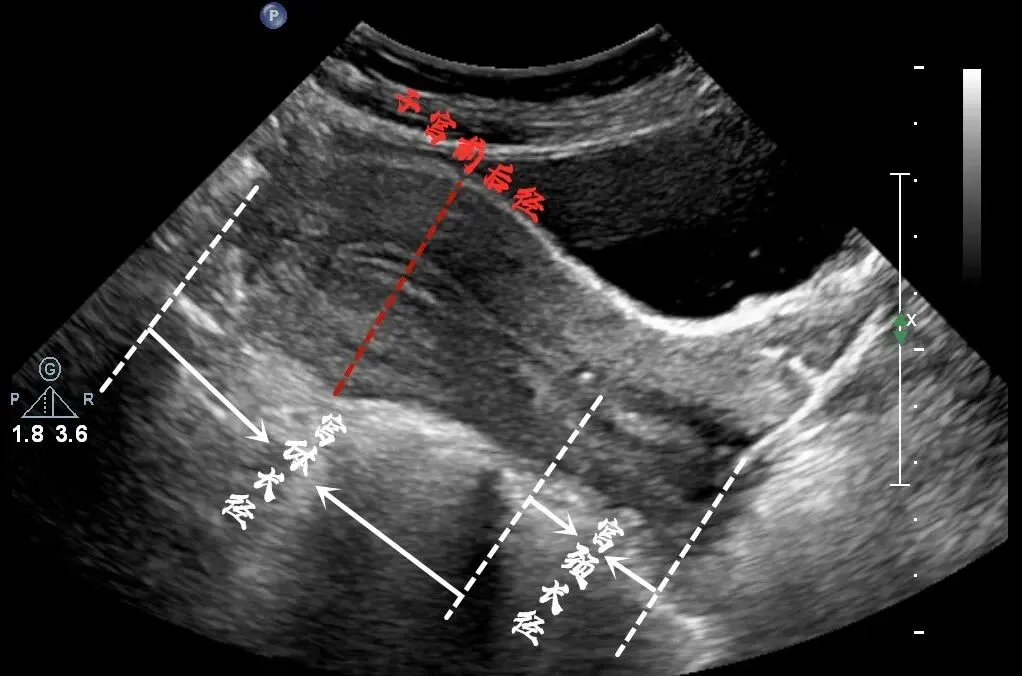

卵巢斜切扫查

仰卧位,扫查右( 左)侧卵巢探头斜置于耻骨联合左(右) 上方,对腹壁适当加压,使声束朝向右( 左)后方,以膀胱做透声窗,显示右(左)侧卵巢。